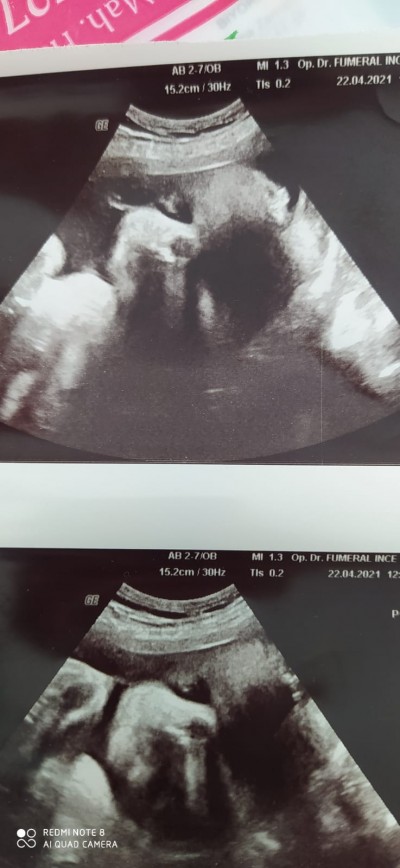

cenesinde çukur var mı doğrumu

Gebelik haftası 33 haftalik

Fotodan hiç bisey anlamadım neyi nasıl ayırt ettiniz ya :D

Bende hiçbirsey anlamadım  fotodan daha bebeğin kafasını ayırt edemedim millet çenesinde.cukur görmüş

Evet fotoğraf yan durmuş ayırt etmek zor oldu çukur gibi duruyor evet

Ayy evet var balll yanaklı yaa maşallah :)

Bende gordum cenesı de gamze gıbı masallah ya saglıkla gelsin evladın

Evet var. Cenesınde gamzesı. Benım oglumunda aynı boyle. Cokta guzel duruyo. Maslallah dıyelım.

Evet çenesine çukur var maşallah çok tatlı Allah size bağışlasın